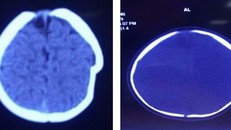

Hình ảnh lún sọ não trước mổ. Ảnh: BSCC.

Chiếc xe tập đi tuột mối dây buộc, lao xuống sân khiến chóp đầu trái của bệnh nhi bị lún sâu 1 cm.